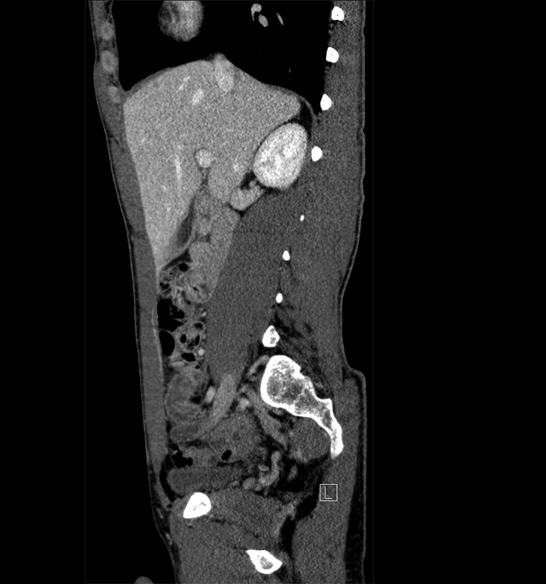

Body

Covers abdominal CT anatomy.